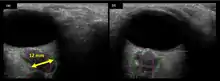

The fourth case of visual changes on orbit was significant for a history of transsphenoidal hypophysectomy for macroadenoma where postoperative imaging showed no residual or recurrent disease. Approximately 2 months into the ISS mission, the astronaut noticed a progressive decrease in near-visual acuity in his right eye and a scotoma in his right temporal field of vision.[5]

Figure 5: On-orbit ultrasound of posterior orbit of the fourth case of visual changes from long-duration spaceflight. In-flight ultrasound image of the right eye showing posterior globe flattening and a raised optic disc consistent with optic-disc edema and raised ICP.

Figure 6: On-orbit ultrasound of optic nerves of the fourth case of visual changes from long-duration spaceflight. In-flight ultrasound shows proximal kinking and increased optic nerve sheath diameter (ONSD) of approximately 12 mm that is consistent with raised ICPs. Optic nerve shown in purple and the ONSD in green.

During the same mission, another ISS long-duration astronaut reported the fifth case of decreased near-visual acuity after 3 weeks of spaceflight. In both cases, CO2, cabin pressure and oxygen levels were reported to be within acceptable limits and the astronauts were not exposed to any toxic fumes.[5]